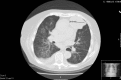

The heart is not too noble to host a metastatic tumor! A right ventricle metastasis of a transitional cell carcinoma of the bladder